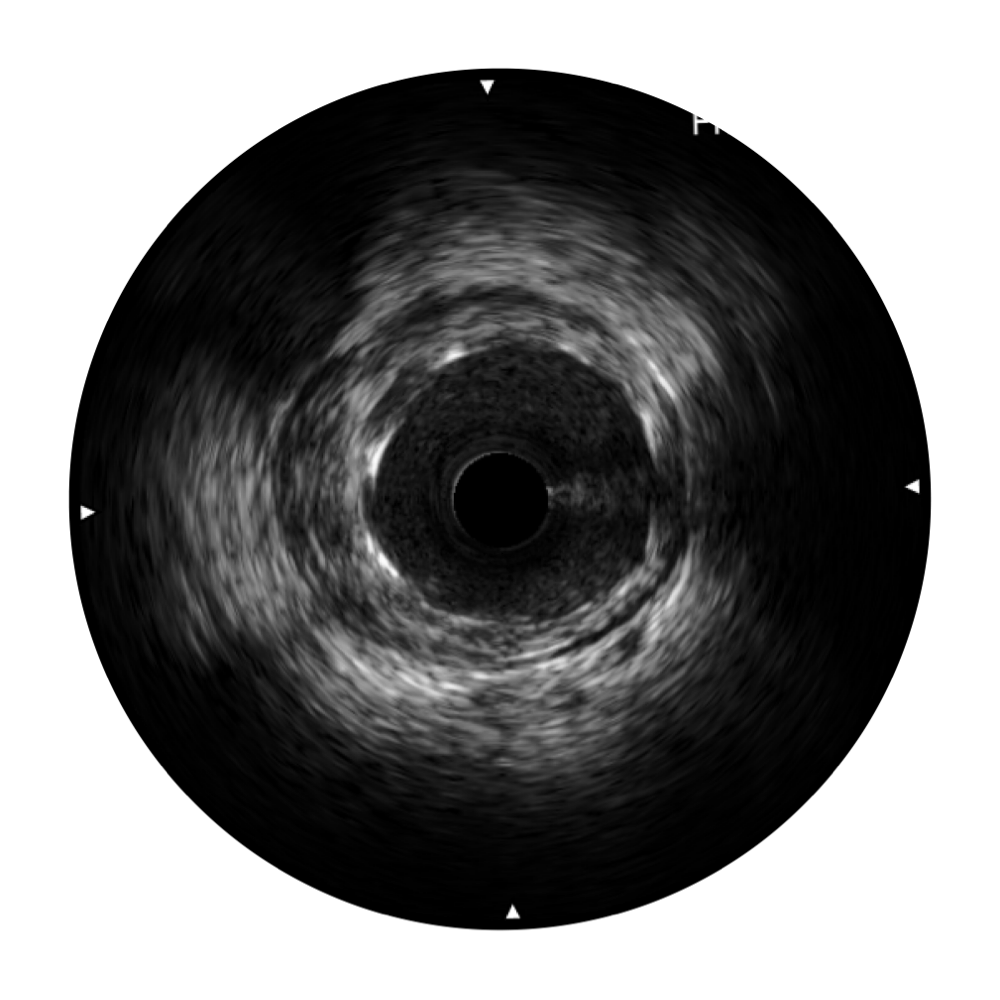

• 玖鼎集团宽频IVUS图像

• 传统IVUS图像

对比传统IVUS导管成像,玖鼎集团宽频IVUS图像的近场支架梁显影更细腻,远场中膜外血管仍清晰可辨,兼顾远中近,兼顾分辨力与穿透深度